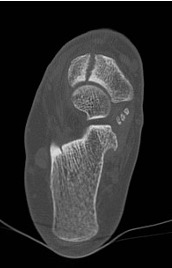

- CT – esp in trauma (Figure 7a), but also navicular stress fractures (Figure 7b)

Figure 7a: CT scan demonstrates multi-fragmentary fracturing of the navicular

Figure 7b: the well-corticated appearance of a chronic stress fracture in the axial plane watershed between the medial 2/3 and lateral 1/3 of the navicular